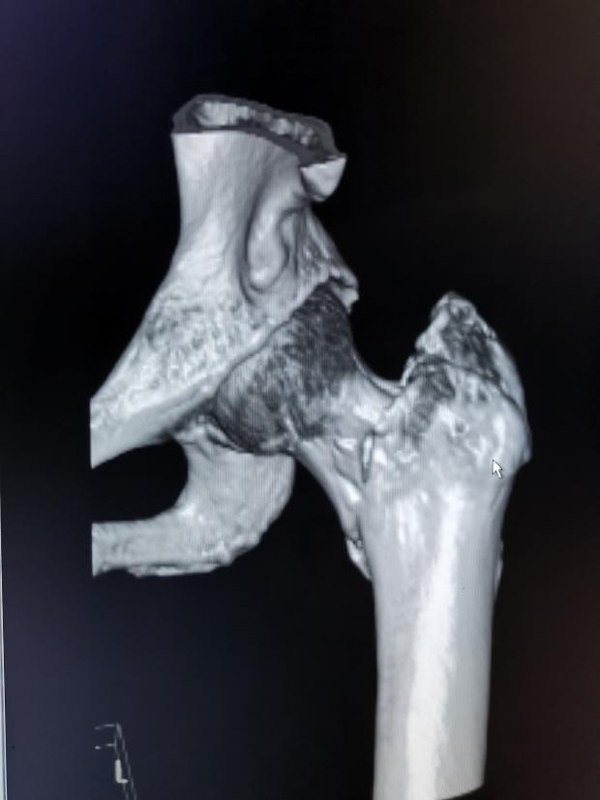

术前三维CT: